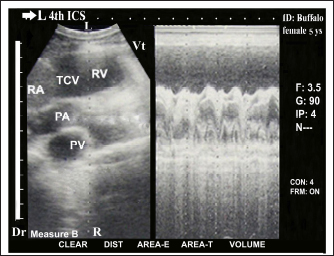

The heart was imaged from the left fourth ICS in midway between the elbow and shoulder points as the angle of the transducer directed dorsally and slightly cranially toward the third ICS, showing visualization of the right ventricular outflow tract (RVOT); RA, RV, TCV, PA, and pulmonary valve (PV) (Fig. 3). Cross sections at the apex of the heart, either in diastole (Fig. 4a) or systole status (Fig. 4b) showed RV and LV. Cross sections in the base of the heart showed RA, LA, TCV, and MV either in diastole (Fig. 5a) or systole status (Fig. 5b). Regular and strong myocardial contractility was clearly observed in both B-mode and m-mode 2-D-gray scale ultrasonography in all buffaloes.

Fig. 3. Echocardiogram of cranial long axis view in adult healthy female non-pregnant (5-year-old) buffalo (left side) using a 3.5 MHz sector 2-D-gray scale transducer (B-mode and M-mode). It was imaged from the left fourth ICS in midway between the elbow point and shoulder point as the transducer directed dorsally and slightly cranial toward the left third ICS. It showed a normal heart with regular, strong contractions and clear margins. The right ventricular RVOT view was imaged whereas it included the RA, RV, TCV, PA, and PV. Dr; Dorsal. Vt; Ventral. R; Right. L; Left.